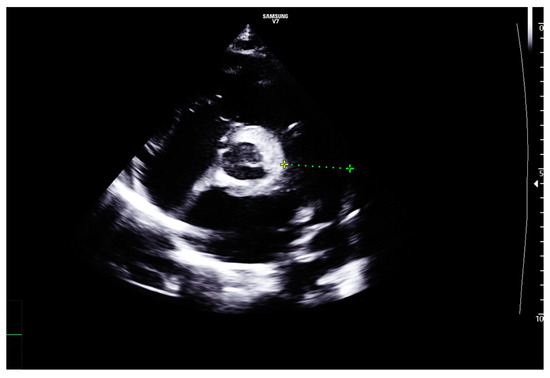

2. Case Report